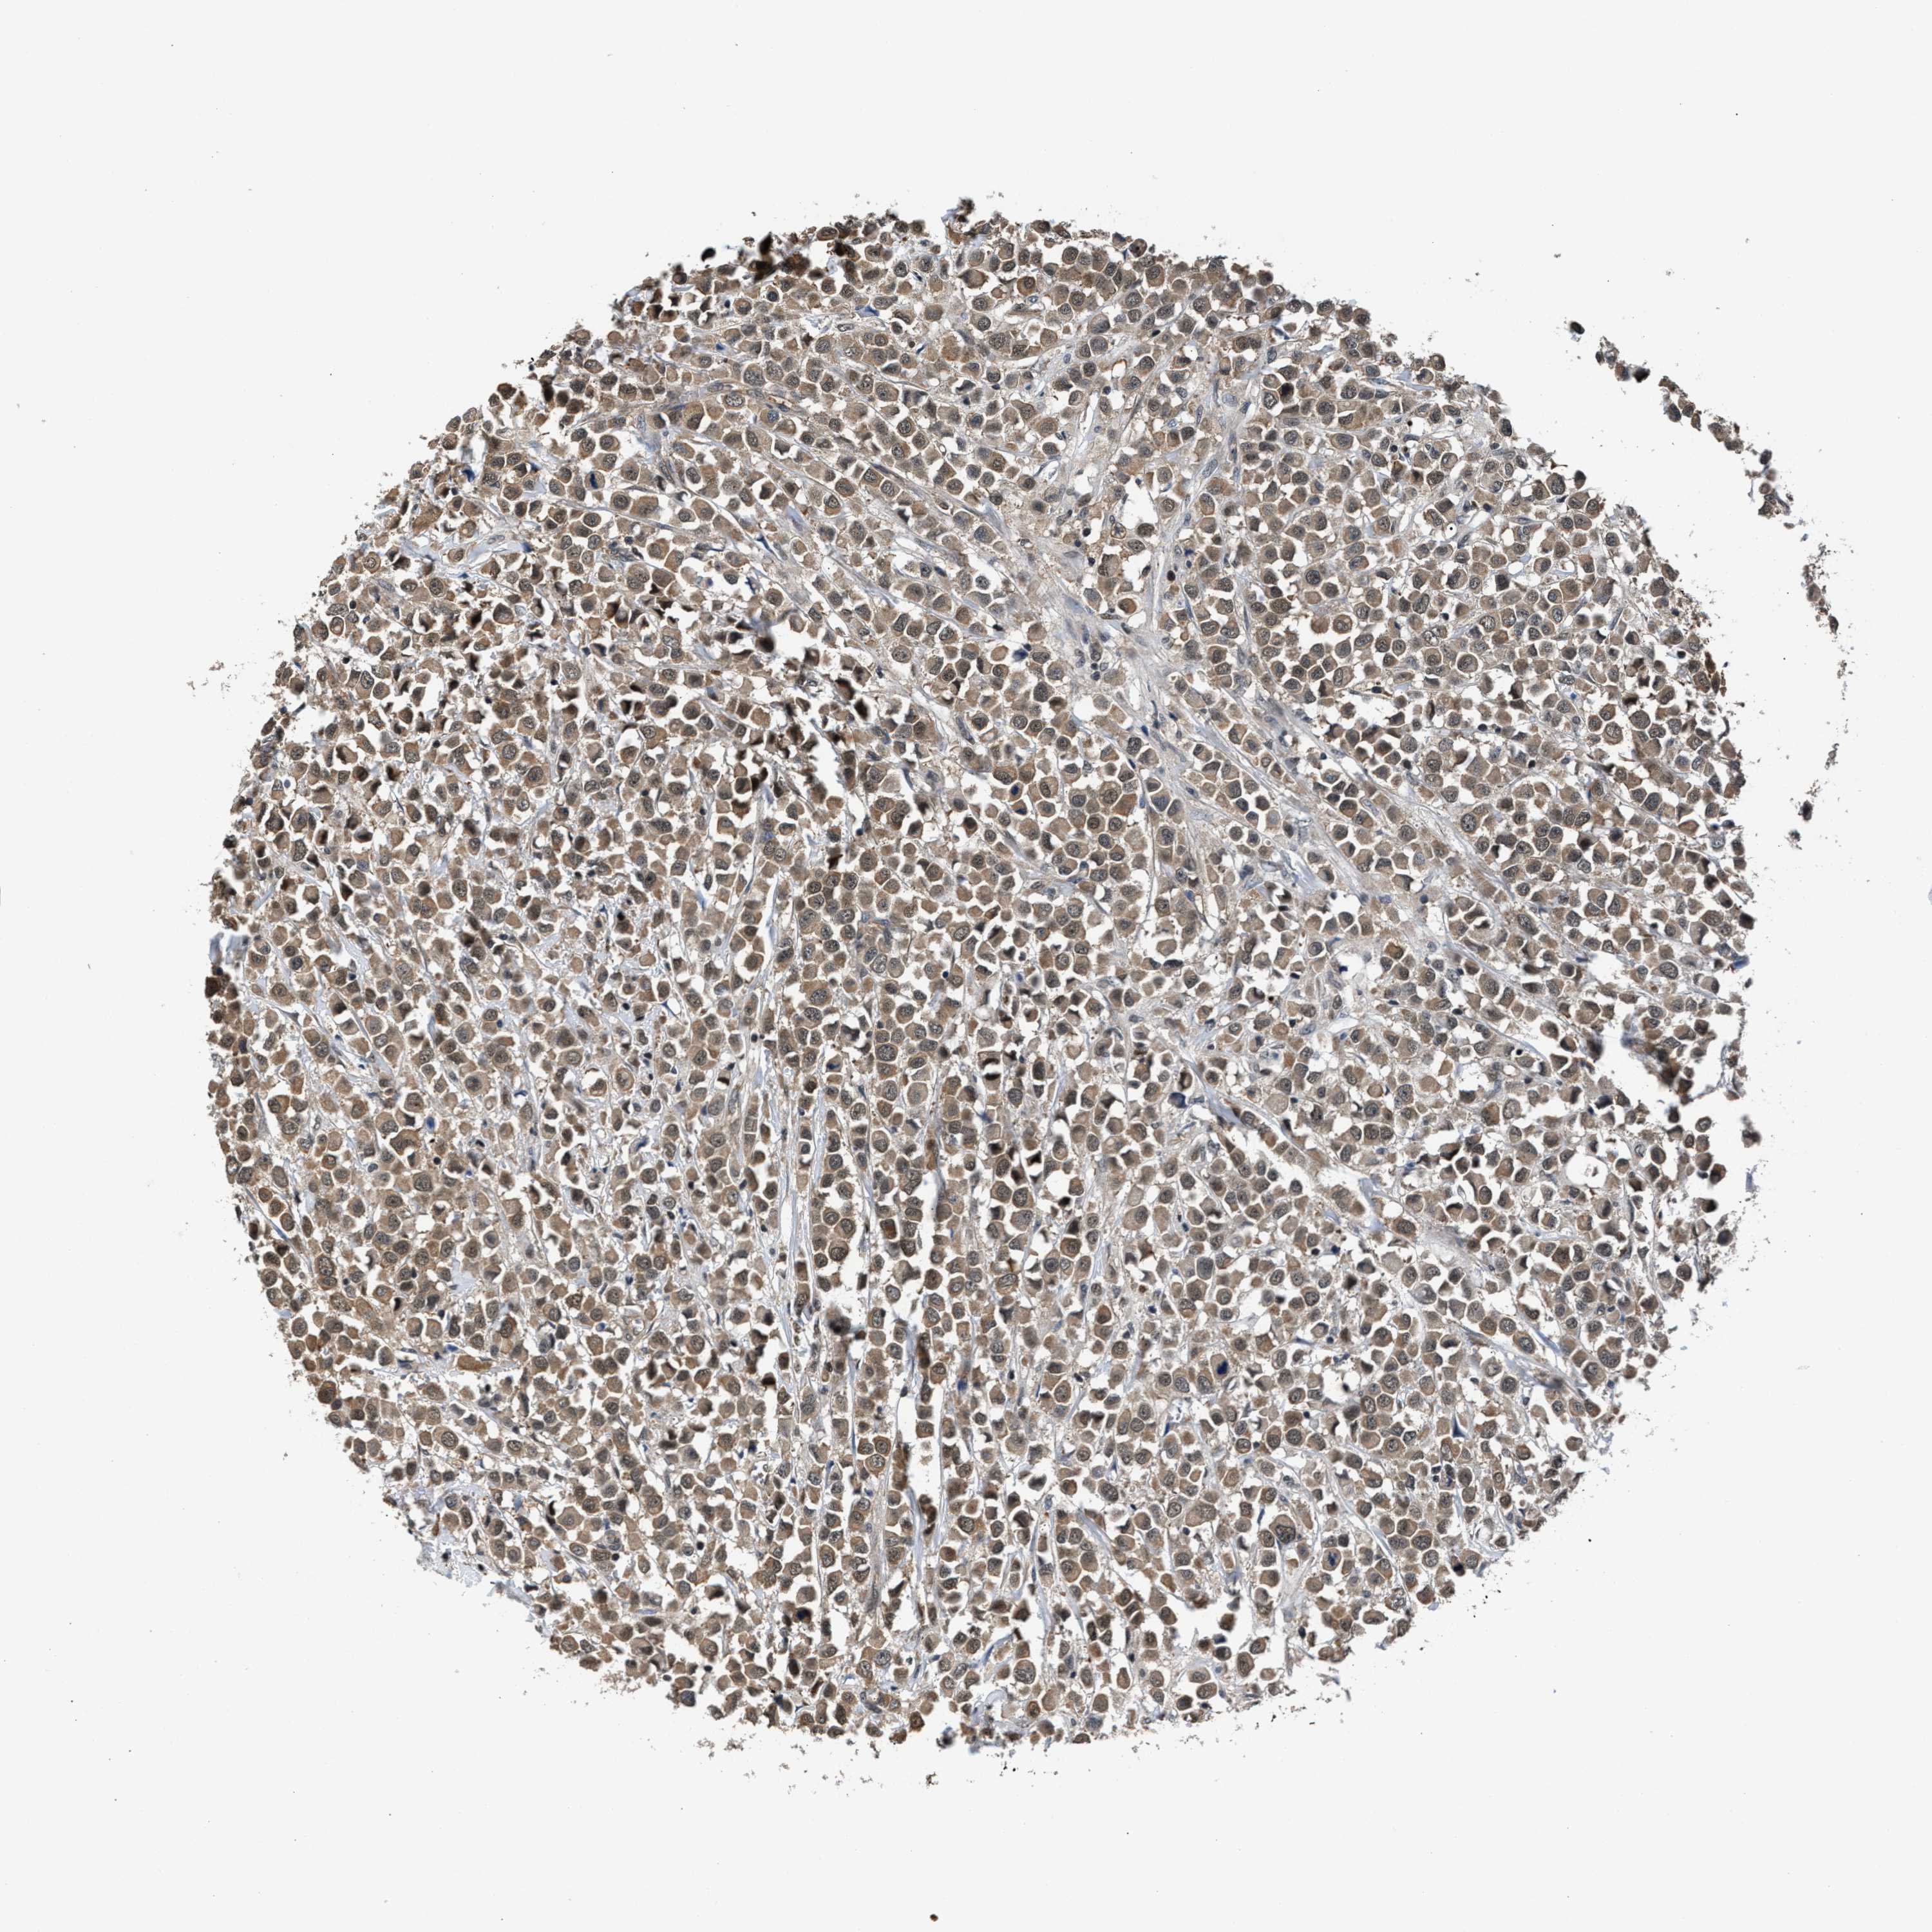

CANCER BREAST CANCER Show tissue menu

BRCA TCGA BRCA VALIDATION PROTEIN EXPRESSION